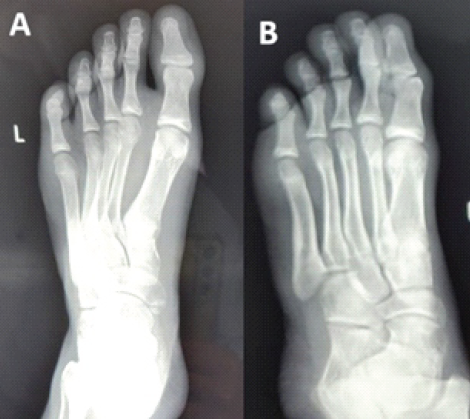

Mechanisms of injury included sports-related trauma, accidental falls, and workplace injuries. Four patients sustained acute injuries, while one presented 3 weeks after trauma with a neglected dislocation. All patients had visible deformity, swelling, and pain of the affected hallux. Standard radiographs confirmed dorsal type II dislocations in four cases and a plantar dislocation in one. True-lateral views were critical in detecting sesamoid incarceration in the delayed case. In all cases, closed reduction failed because the interposed sesamoid bone acted as a mechanical block, preventing congruent reduction of the IP joint. Open reduction was performed in all patients: through medial, dorsal, or L-shaped approaches, depending on chronicity and soft-tissue involvement. Temporary Kirschner-wire fixation was required in all cases to address capsuloligamentous instability. All procedures were performed by a single person (senior author). We present a case of Miki type II dorsal dislocation of the great toe IP joint with incarcerated sesamoid, demonstrating the stepwise approach and management. All the cases were dealt similarly, as described below. Here is an example of a case with a pre-operative radiograph as shown in Fig. 1.

Figure 1: This is a preoperative image of an interphalangeal joint dislocation of the great toe with an incarcerated sesamoid, as shown in anteroposterior, oblique, and lateral images of the left foot (a, b, c).